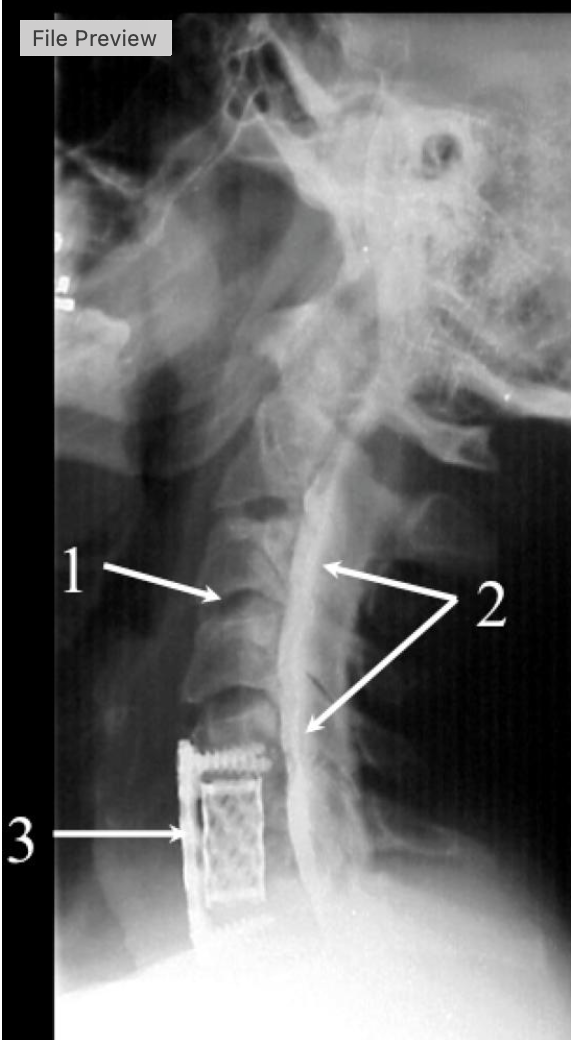

what procedure is being performed

cervical myelogram

what intervertebrak disk space is at #1

C3-C4